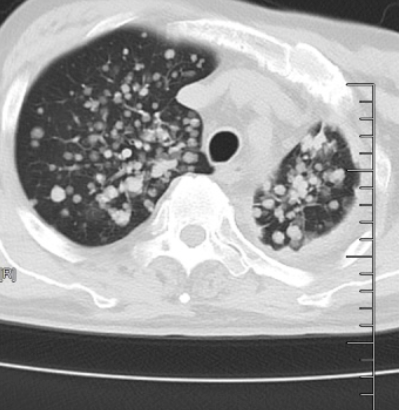

△原发性肺癌伴双肺弥漫多发转移瘤

庄兴俊主任给患者安排了胸部CT,检查结果很快传来:原发性肺癌伴双肺弥漫多发转移瘤,双肺胸膜弥漫增厚,纵隔淋巴结也已被肿瘤侵犯,肺部成了肿瘤蔓延重灾区。